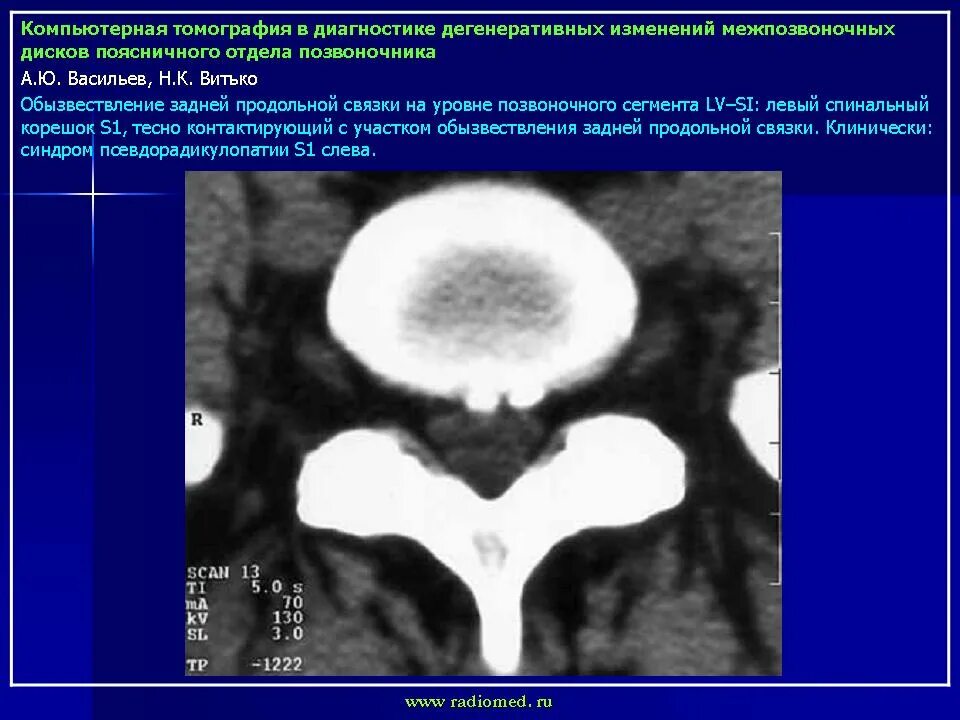

Мрт признаки дегенеративных изменений